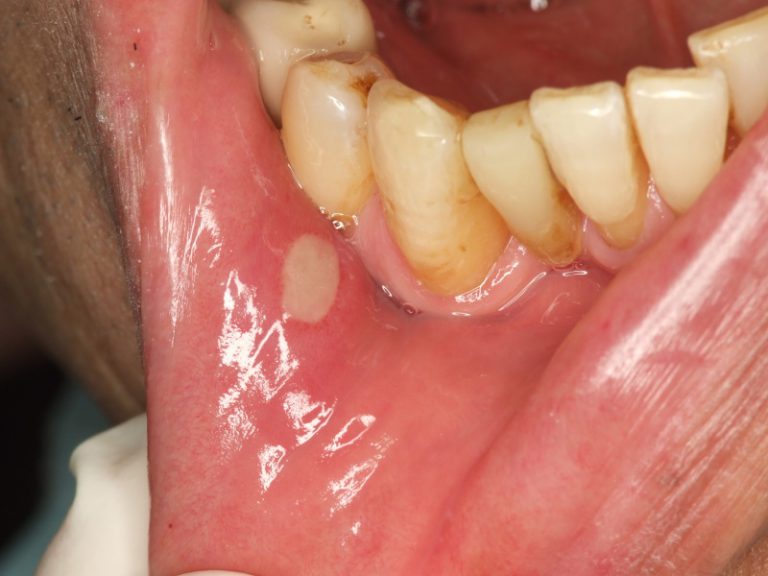

口内炎またはアフタ性潰瘍は、口の中や周囲に現れる、小さくて丸い痛みを伴う潰瘍です。通常、中心は黄色、白、または灰色で、周囲に赤いリングがある場合があります。

口内炎の種類が異なれば、症状の現れ方も異なり、再発の頻度も高くなります。より大きな口内炎は、より痛みを伴います。

口内炎には主に 3 つのタイプがあります。

- 軽度の口内炎:最も一般的なタイプで、小さな口内炎が発生し、瘢痕化することなく約 1 週間で治癒します。それらは約 85% の人に影響を及ぼします。

- 重度の口内炎:症例の約 10% のみに存在し、これらの傷は軽度の口内炎よりも大きく、2 週間以上続きます。傷は非常に痛みを伴い、傷跡が残る場合があります。

- ヘルペス状口内炎このタイプに罹患する人は 5% 未満で、小さな潰瘍が集団で発生し、治癒までに約 1 週間かかります。これらはすぐに再発する可能性があり、1 つの大きな潰瘍に合併して瘢痕が残る場合もあります。